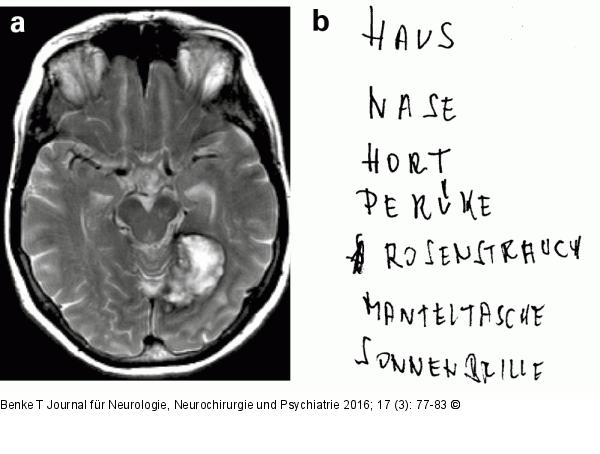

Abbildung 4a-b: Lesestörung-Alexie 66-jährige Patientin mit schwerer Lesestörung (reine Alexie, Alexie ohne Agraphie; Störung des lexikalischen Lesens und Fehlidentifikation einzelner Buchstaben) 4a: Im MRT spontane Blutung okzipito-temporal links 4b: Erhaltenes Schreiben nach Diktat. Pat. kann schreiben, Geschriebenes jedoch nicht flüssig lesen. Der Therapieansatz bestand in einer aufbauenden buchstaben- und wortbasierten Übungsbehandlung zur Verbesserung der Lesegeschwindigkeit und zur Fehlervermeidung. |

66-jährige Patientin mit schwerer Lesestörung (reine Alexie, Alexie ohne Agraphie; Störung des lexikalischen Lesens und Fehlidentifikation einzelner Buchstaben) 4a: Im MRT spontane Blutung okzipito-temporal links 4b: Erhaltenes Schreiben nach Diktat. Pat. kann schreiben, Geschriebenes jedoch nicht flüssig lesen. Der Therapieansatz bestand in einer aufbauenden buchstaben- und wortbasierten Übungsbehandlung zur Verbesserung der Lesegeschwindigkeit und zur Fehlervermeidung. |